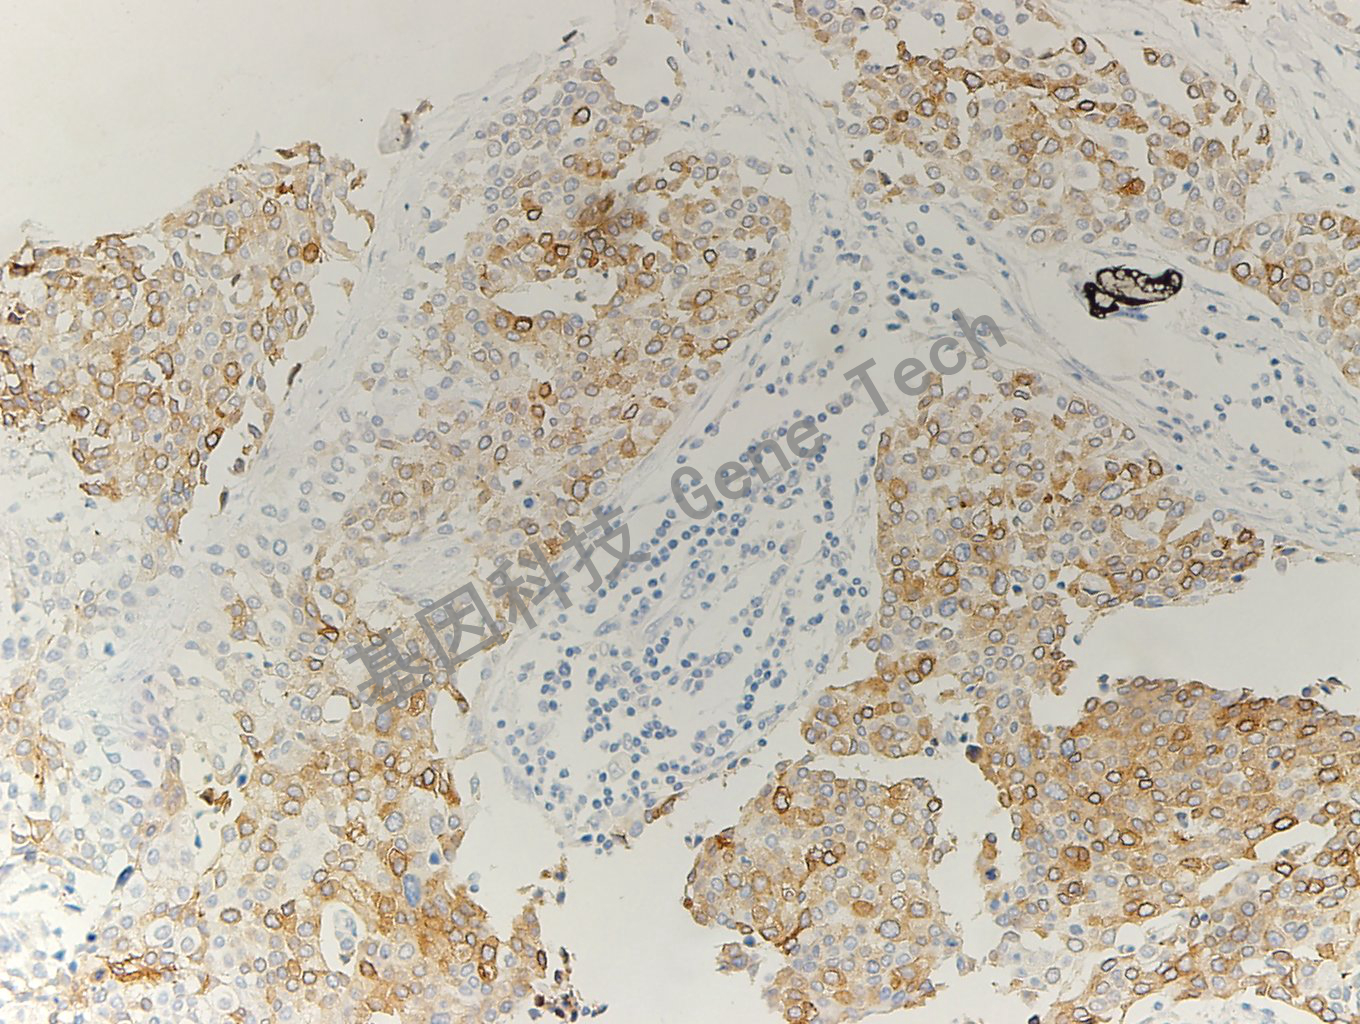

膀胱癌石蜡切片,用 Uroplakin Ⅱ(GT2423)染色,细胞膜/细胞浆阳性,DAB 显色。

Uroplakins II是尿路上皮细胞分化特异性糖蛋白,主要表达在尿路移行上皮的伞状细胞层,中间层细胞也有少量表达,是移行细胞癌的标记物,呈移行上皮特异性、分化依赖性表达,对转移灶的诊断极其重要。UroplakinII和UroplakinIII一样特异,而敏感度更高。